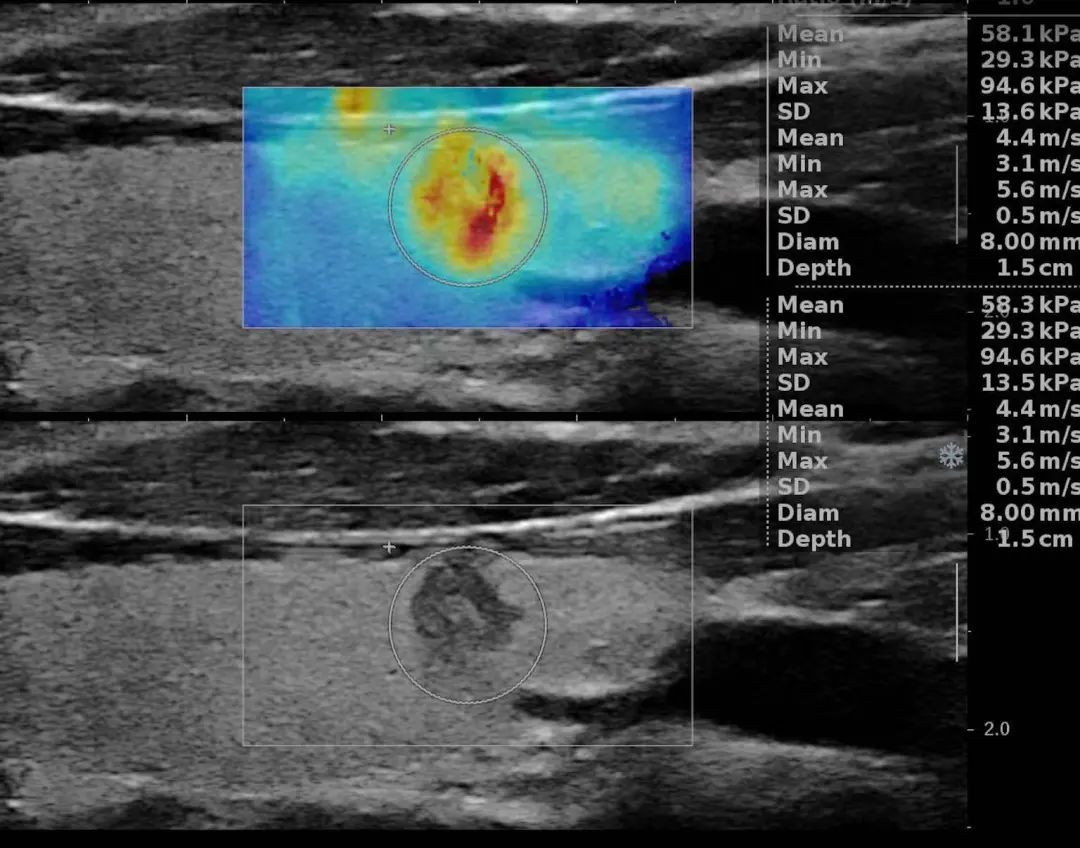

皮肤小包“良恶”难辨?多模态超声精准揪出“危险分子”!

...

甲状腺乳头状微小癌剪切波和二维图像对比...